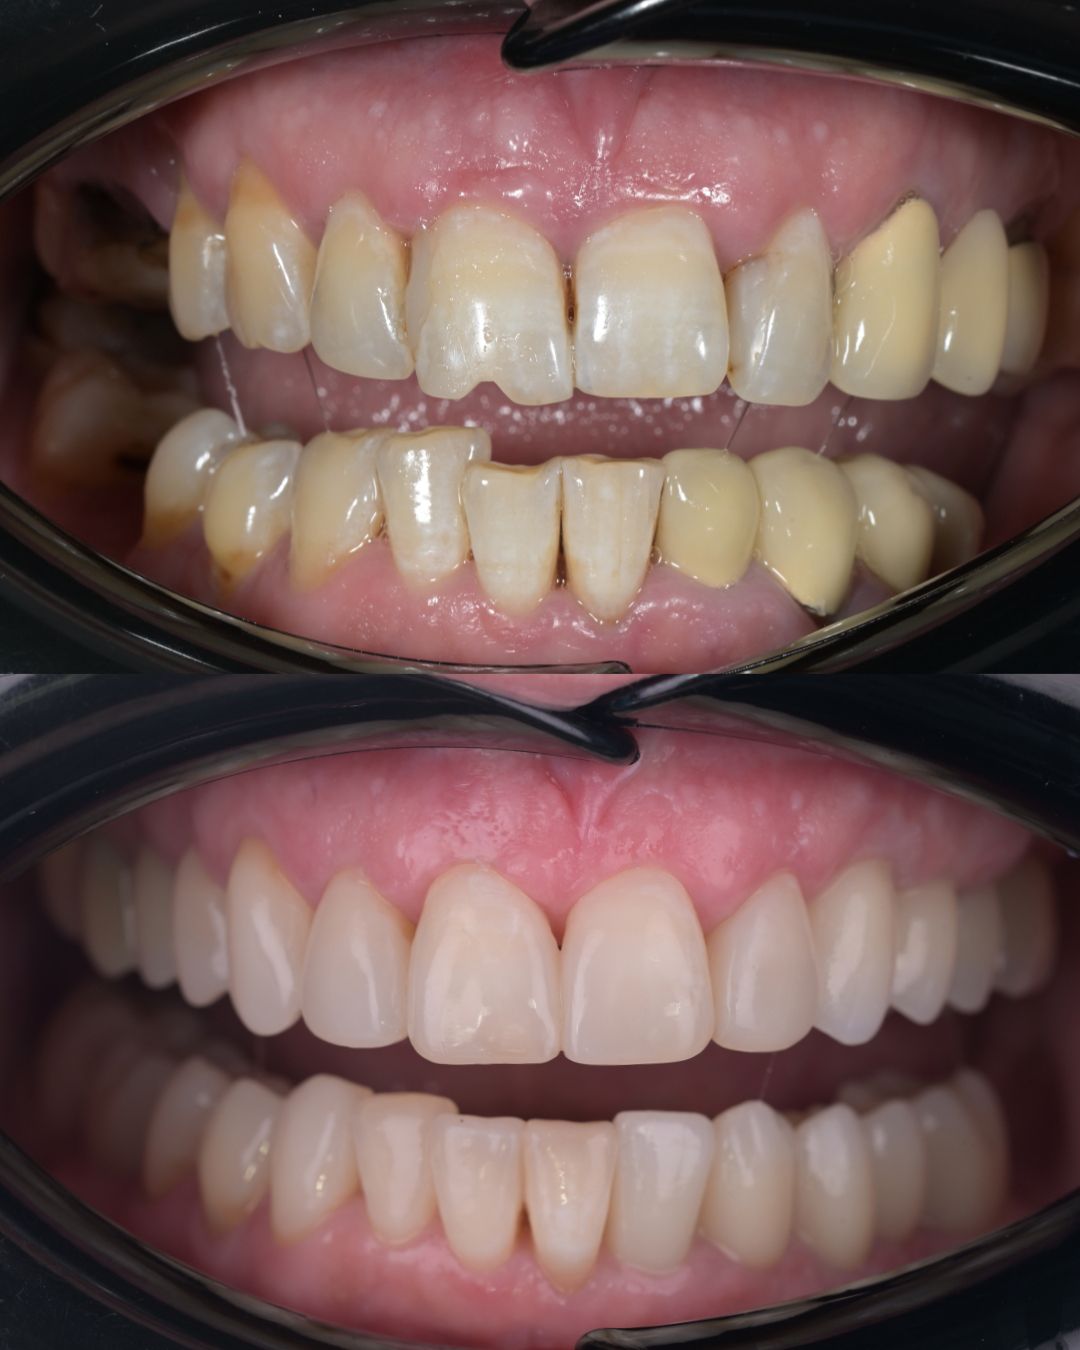

до и после